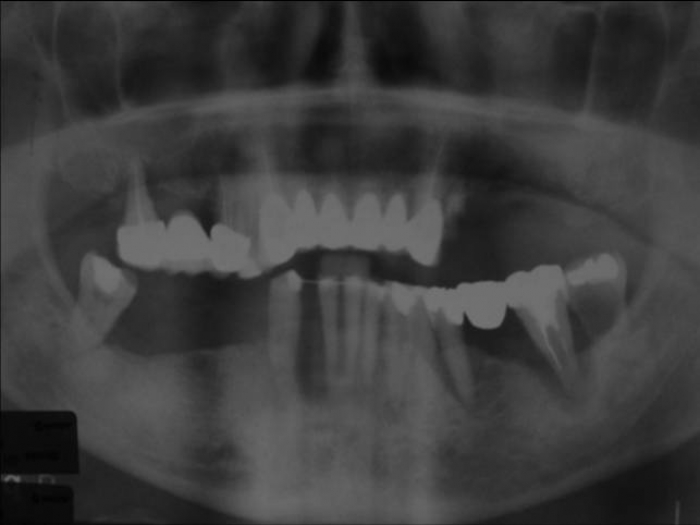

Raio X inicial